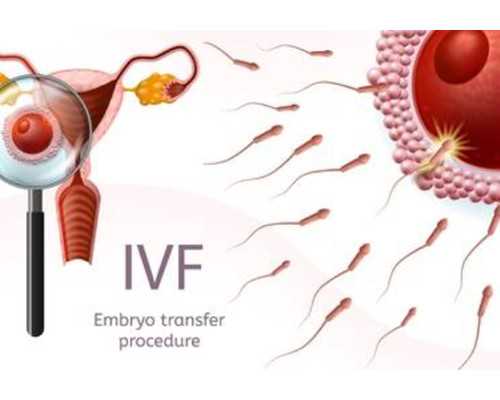

無錫成功寶貝助孕代孕套餐秉承美國醫療服務模式,主要開展第三代試管嬰兒,零風險包成功無效退款,專業的三代試管醫療團隊為您提供專業的助孕試管服務!

在試管嬰兒這項手術實施過程當中,可以結合實際情況來分為很多不同的類型,比如當你決定在無錫做試管嬰兒手術的時候,你可能會考慮到在無錫做試管嬰兒的手術價格,那么這種情況下每一個人都有自己的想法,有的人也在思考無錫做試管嬰兒費用究竟是多少,從目前的情況來看,如果你真的決定在這里做試管嬰兒手術的話,那么對于他們的費用,大家要從各個角度來看,人工授精和試管嬰兒的費用多多少少都會有所不同。

人工授精費用價格相對便宜,因為他的就是女性輸卵管要通暢,適合于男性的性功能障礙,如果男性本身沒有精子的話,也可以考慮做人工受精,所以說這種情況下的價格相對于試管嬰兒來說會更加便宜一點,試管嬰兒適合那些輸卵管不通暢,不管哪些是否正常都可以選擇做試管嬰兒,而且是管嬰兒能夠對基因進行篩查,但是試管嬰兒的價格可能會是人工授精的兩倍。

促排卵過程不同

不管是人工授精還是試管嬰兒,他們的促排卵的過程多多少少的都會有所不同,人工授精是可以促排卵,也可以自然來進行排卵,而食管嬰兒必須要選擇超出排卵,也就是說他們在做試管嬰兒的過程當中會一次性提取20多個卵子,這樣的話才能夠配置成各種不同的胚胎,從而在無形當中增加試管嬰兒成功率,有效降低試管嬰兒費用。一次性的促排卵費用,可能價格也在1萬元到2萬元之間。

手術方法不同

其實在選擇試管嬰兒手術的時候,你會發現人工授精和試管嬰兒,這是兩種完全不同的手術,而且這兩種手術的差別也會非常的大,人工受精的手術費用的價格差不多也就在2000元左右,試管嬰兒的手術的價格要根據取卵或者是體外受精的情況來進行了解,一般來說在這其中要做好相關的胚胎移植或者是胚胎的冷凍,總體的費用差不多也就在1萬元到2萬元之間。